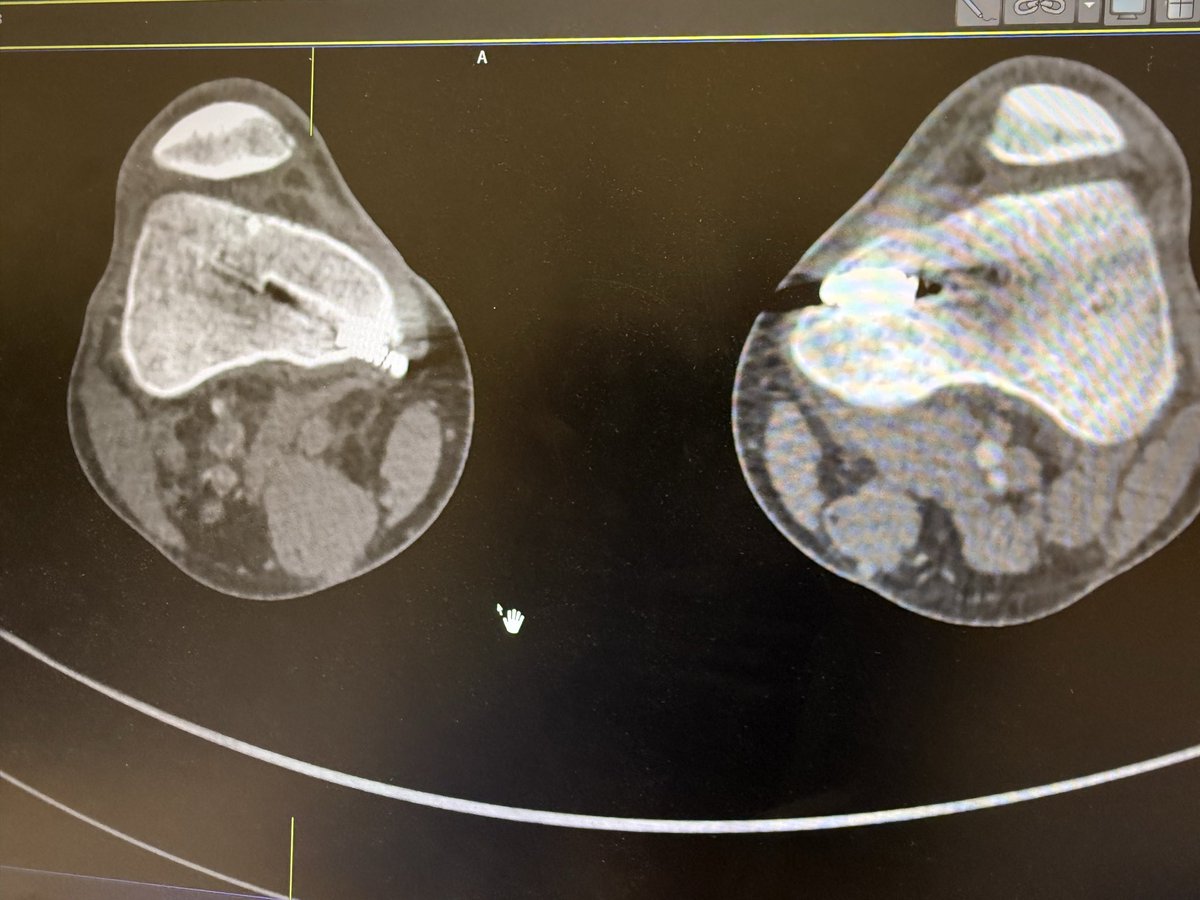

#vasctwitter 17 yrs old male, keen football player.sudden onset pain in right leg and foot. Absent foot pulses and pale foot. CTA below. What is the diagnosis? Look at cross sectional image?! How would you treat?